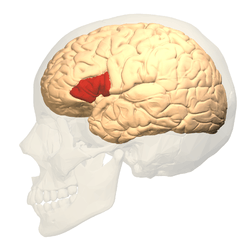

Modern neuroimaging techniques such as functional magnetic resonance imaging (fMRI) and positron emission tomography (PET) have shown a correlation between both functional and structural differences in the brains of children with reading difficulties.[47] Some dyslexics show less electrical activation in parts of the left hemisphere of the brain involved with reading, such as the inferior frontal gyrus, inferior parietal lobule, and the middle and ventral temporal cortex.[41] Over the past decade, brain activation studies using PET to study language have produced a breakthrough in the understanding of the neural basis of language. Neural bases for the visual lexicon and for auditory verbal short-term memory components have been proposed,[48] with some implication that the observed neural manifestation of developmental dyslexia is task-specific (i.e. functional rather than structural). fMRIs in dyslexics have provided important data which point to the interactive role of the cerebellum and cerebral cortex as well as other brain structures.[49][50]

In phonological dyslexia, sufferers can read familiar words but have difficulty with unfamiliar words, such as invented pseudo-words.[80] Phonological dyslexia is associated with lesions in the parts of the brain supplied with blood by the middle cerebral artery. The superior temporal lobe is often also involved. Furthermore, dyslexics compensate by overusing a front-brain region called Broca's area, which is associated with aspects of language and speech.[81] The Lindamood Phoneme Sequencing Program (LiPS) is used to treat phonological dyslexia.[82] This system is based on a three-way sensory feedback process, using auditory, visual, and oral skills to learn to recognize words and word patterns. Case studies with a total of three patients found a significant improvement in spelling and reading ability after using LiPS.[83]